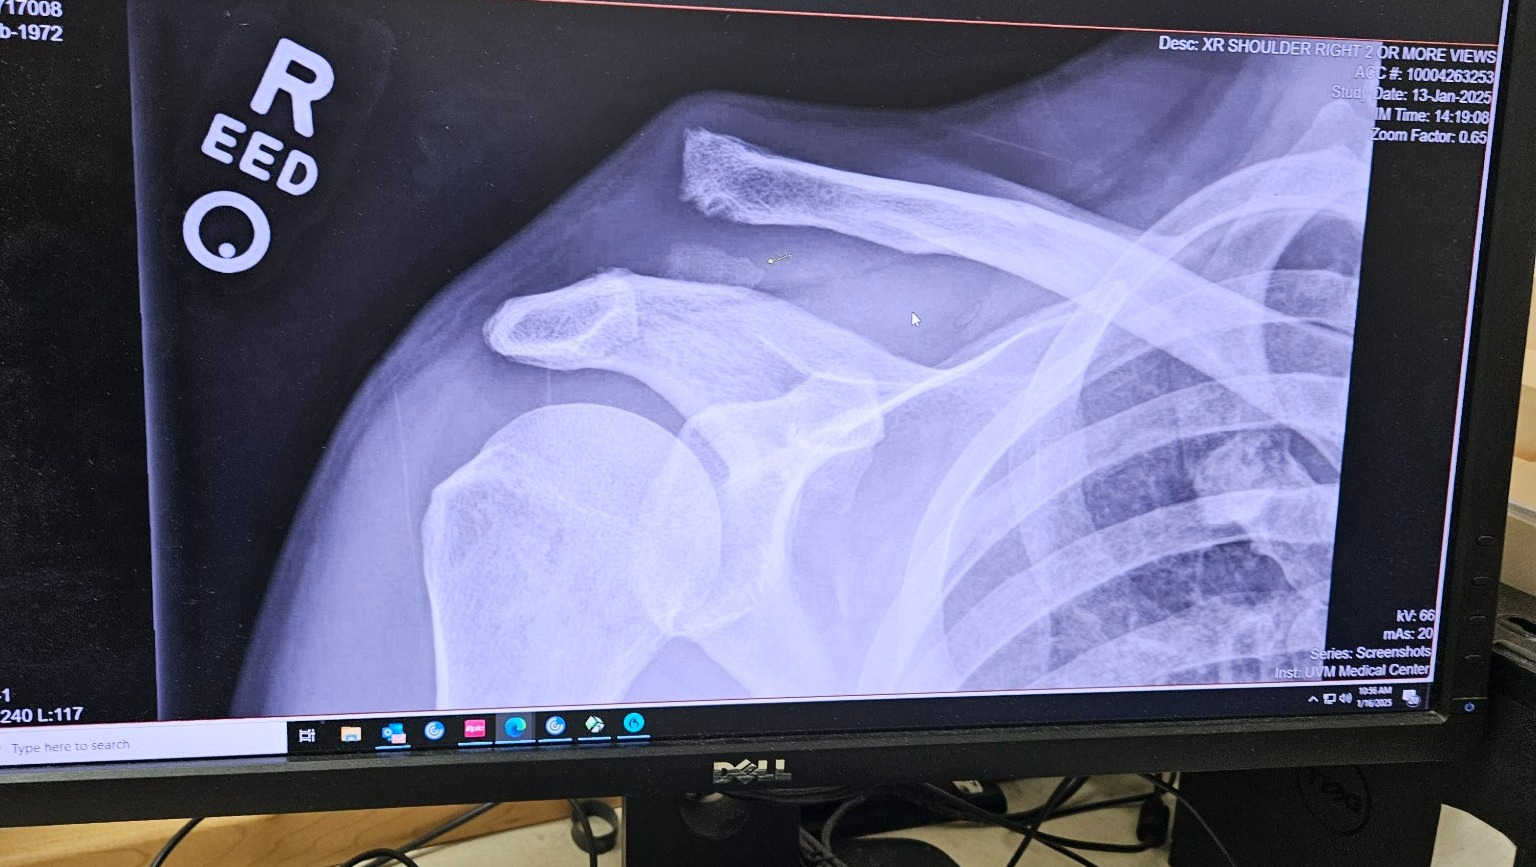

Our dear friend Billy Gunning needs our help! In October, Billy suffered a debilitating injury, breaking his collarbone and fully dislocating it from his scapula. The severity of this injury will require surgery and a 12-24 week recovery, during which he will be unable to work. As a builder and musical artist, Billy lives by the work of his hands and this surgery is essential to his well-being and that of his family. Please consider making a donation so he will have the resources needed for his recovery and medical expenses. Together we can be there for this beloved member of our community and help him get back to making music and building homes! All support is deeply appreciated.